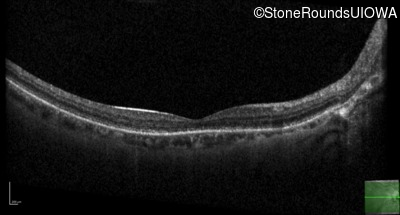

Optical Coherence Tomography - Right - 20/32 -1

Exemplar / OCT Stack

OCT Stack